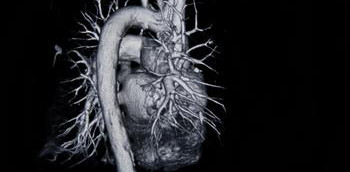

La raíz de aorta es la parte más proximal de la aorta. Se extiende desde el anillo aórtico hasta la unión sinotubular. Funciona como una estructura de soporte para la válvula aórtica, da origen a las arterias coronarias y se prolonga distalmente con la aorta...